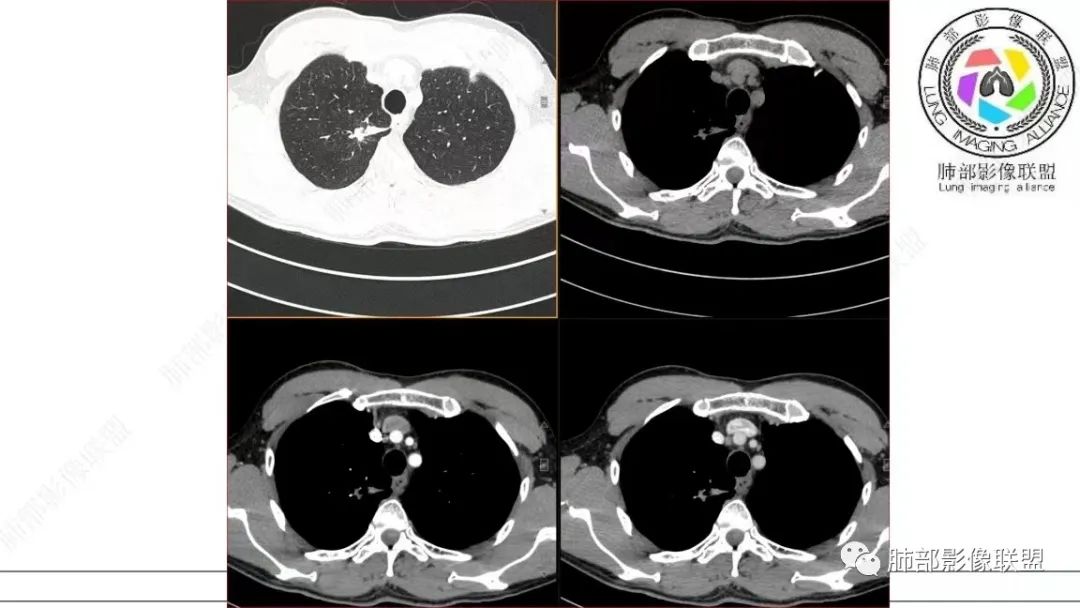

飞鹰行动:中年男性,右肺上叶不规则病灶,与胸膜粘连,多发长毛刺,周围模糊的磨玻璃影,相邻胸膜增厚,增强病灶中度以上强化,内见血管影,没有重建图像,感觉病灶符合良性病变征象多一些,考虑炎性病变,OP?

小兜:男,50岁,体检发现右肺上叶胸膜下不规则软组织结节,分叶,长毛刺,与胸膜相连,胸膜增厚,渐进性强化,强化不均匀,内部可见小灶状低强化灶,内部血管穿行。首先考虑肉芽肿性病变,鉴别腺癌

衡妈:中年男性,右肺上叶尖段不规则实性病灶,边缘多深分叶局部形似并见数条长毛刺,与胸膜面数条牵拉中年男性,右肺上叶尖段不规则实性病灶,边缘多深分叶局部形似枫叶,侧胸膜局部幕状增厚,病灶增强后不均匀中等强化。考虑恶性肿瘤,腺癌可能,鉴别炎性肉芽肿(结核)、炎性肌纤维母细胞瘤。

谢加平:右肺上叶尖段内侧胸膜下分叶状结节,不规则,见尖角状凸起,边缘支气管锥形中断,实性不均匀强化,血管进入增粗和集血管束特点,宽基底胸膜牵拉,形成兔耳征,冠状面结节外侧见指头状凸起,恶性特点明显,支持浸润性腺Ca。

细支气管腺瘤的病理要点中,很重要的一点就是双层细胞。返回来看影像,这个病变还是很有特点的,诊断结核确实有点不合适。一点点的看。

仔细看,里面是有低密度的。平扫CT值也很低,才16HU。

增强也很有特点。这些低密度,是有延迟强化特点的。

平扫低密度,就这个病变而言,我们最容易想到的:干酪性坏死、黏液。而延迟强化。所以这个病变是不符合干酪性坏死的表现的。很多平直凹陷的地方,与胸膜宽基底接触,是否存在胸膜牵拉不详,需重建看看。说明这个病变是有收缩力的。里面含有一部分纤维。当然,含有纤维的,肿瘤的肌成纤维可以,上皮间质转换可以,慢性炎也可以,好多病变里面可以有纤维。干酪样坏死,是不会强化的。延迟强化,肉芽肿可以,纤维比较多的或者黏液多的也可以。

还是和病变成分有关。在肿瘤当中,或者上皮间质转换比较明显等,可以有不同的强化方式。当然也可以表现为延迟强化,可以动脉期明显强化。和肿瘤的具体类型,以及具体病变的病理成分有关。多层面观察,病变是明确有细支气管进入的,而且明确的有铸型的低密度粘液栓。